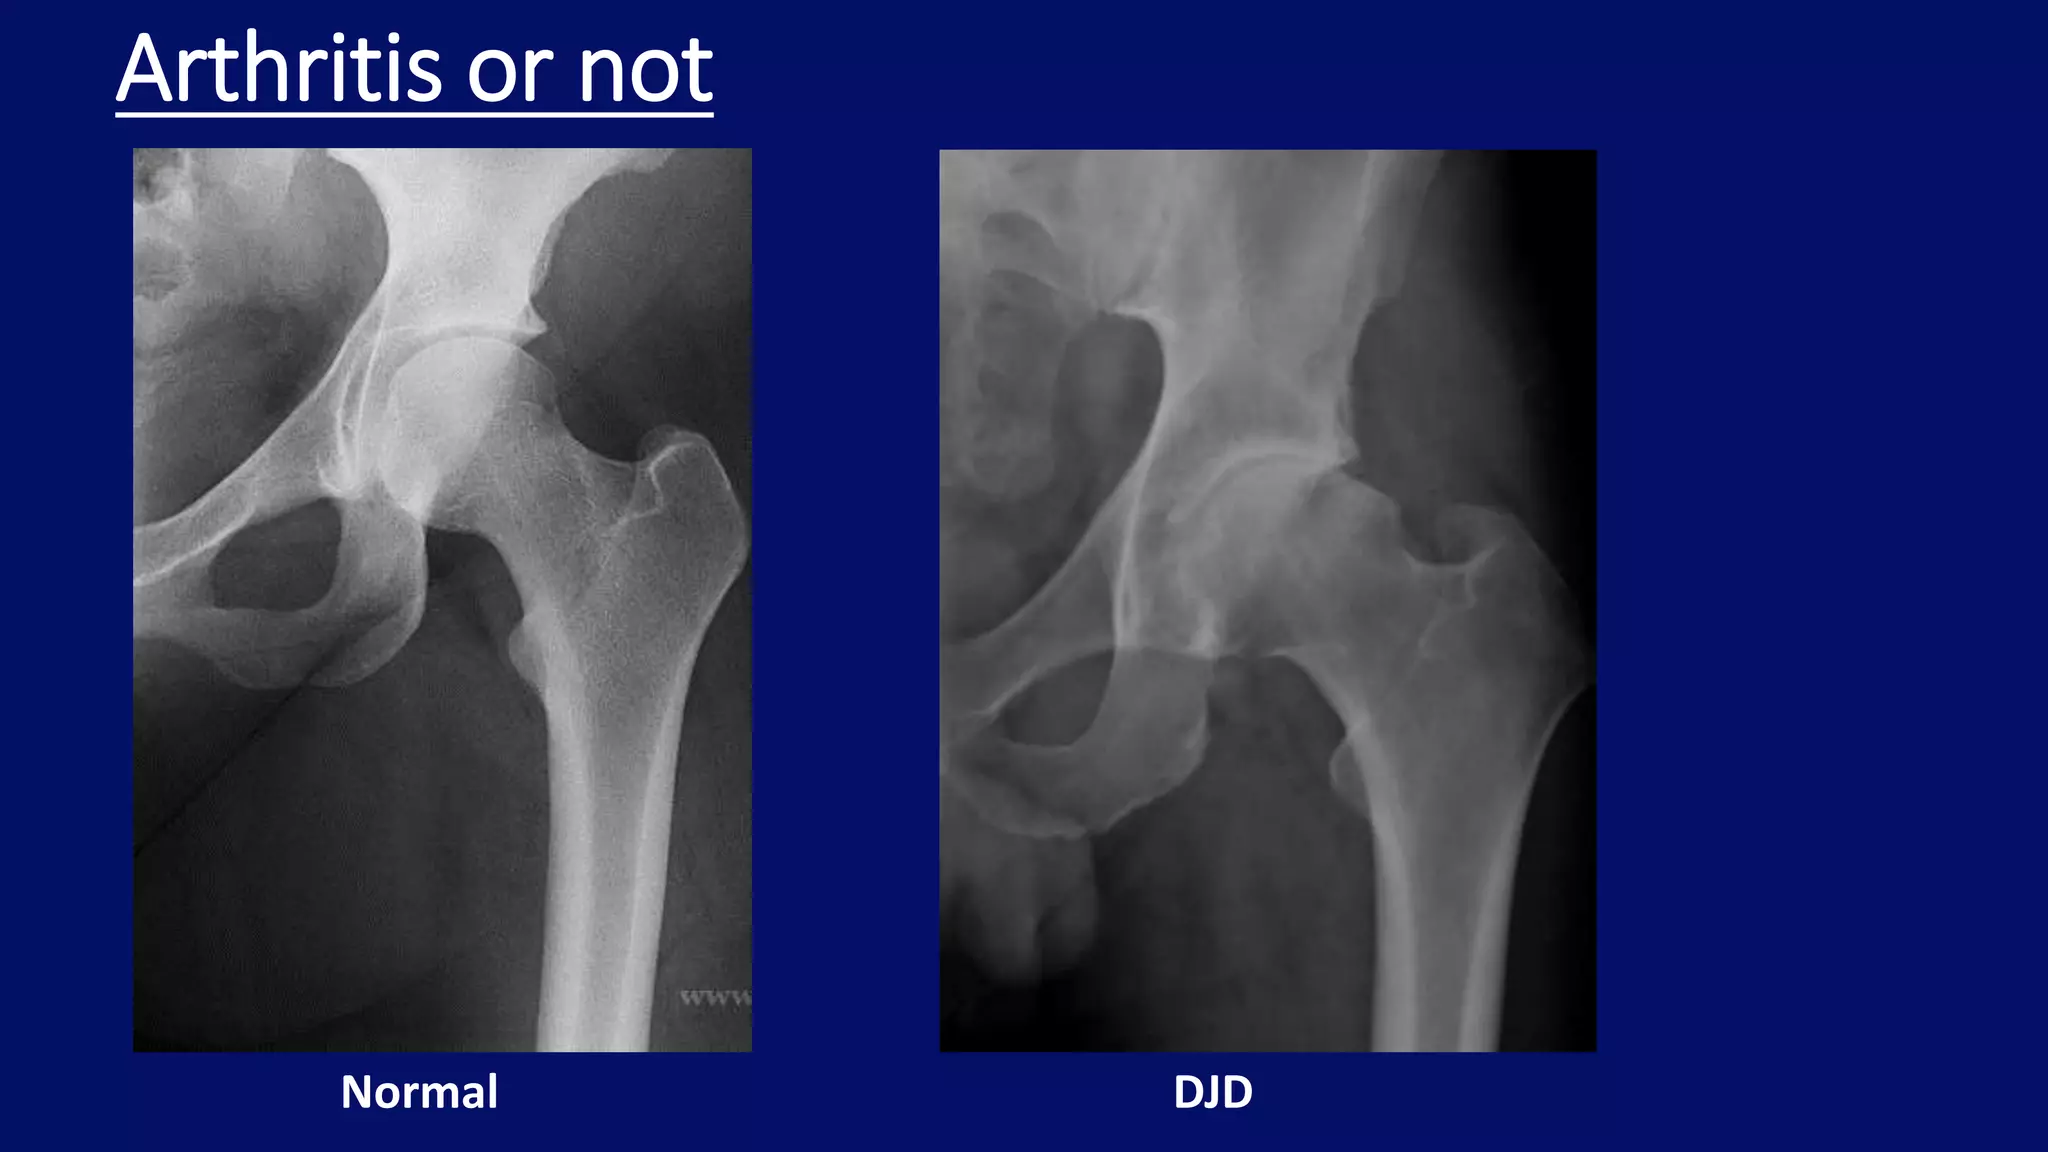

Arthritis or not

Normal DJD